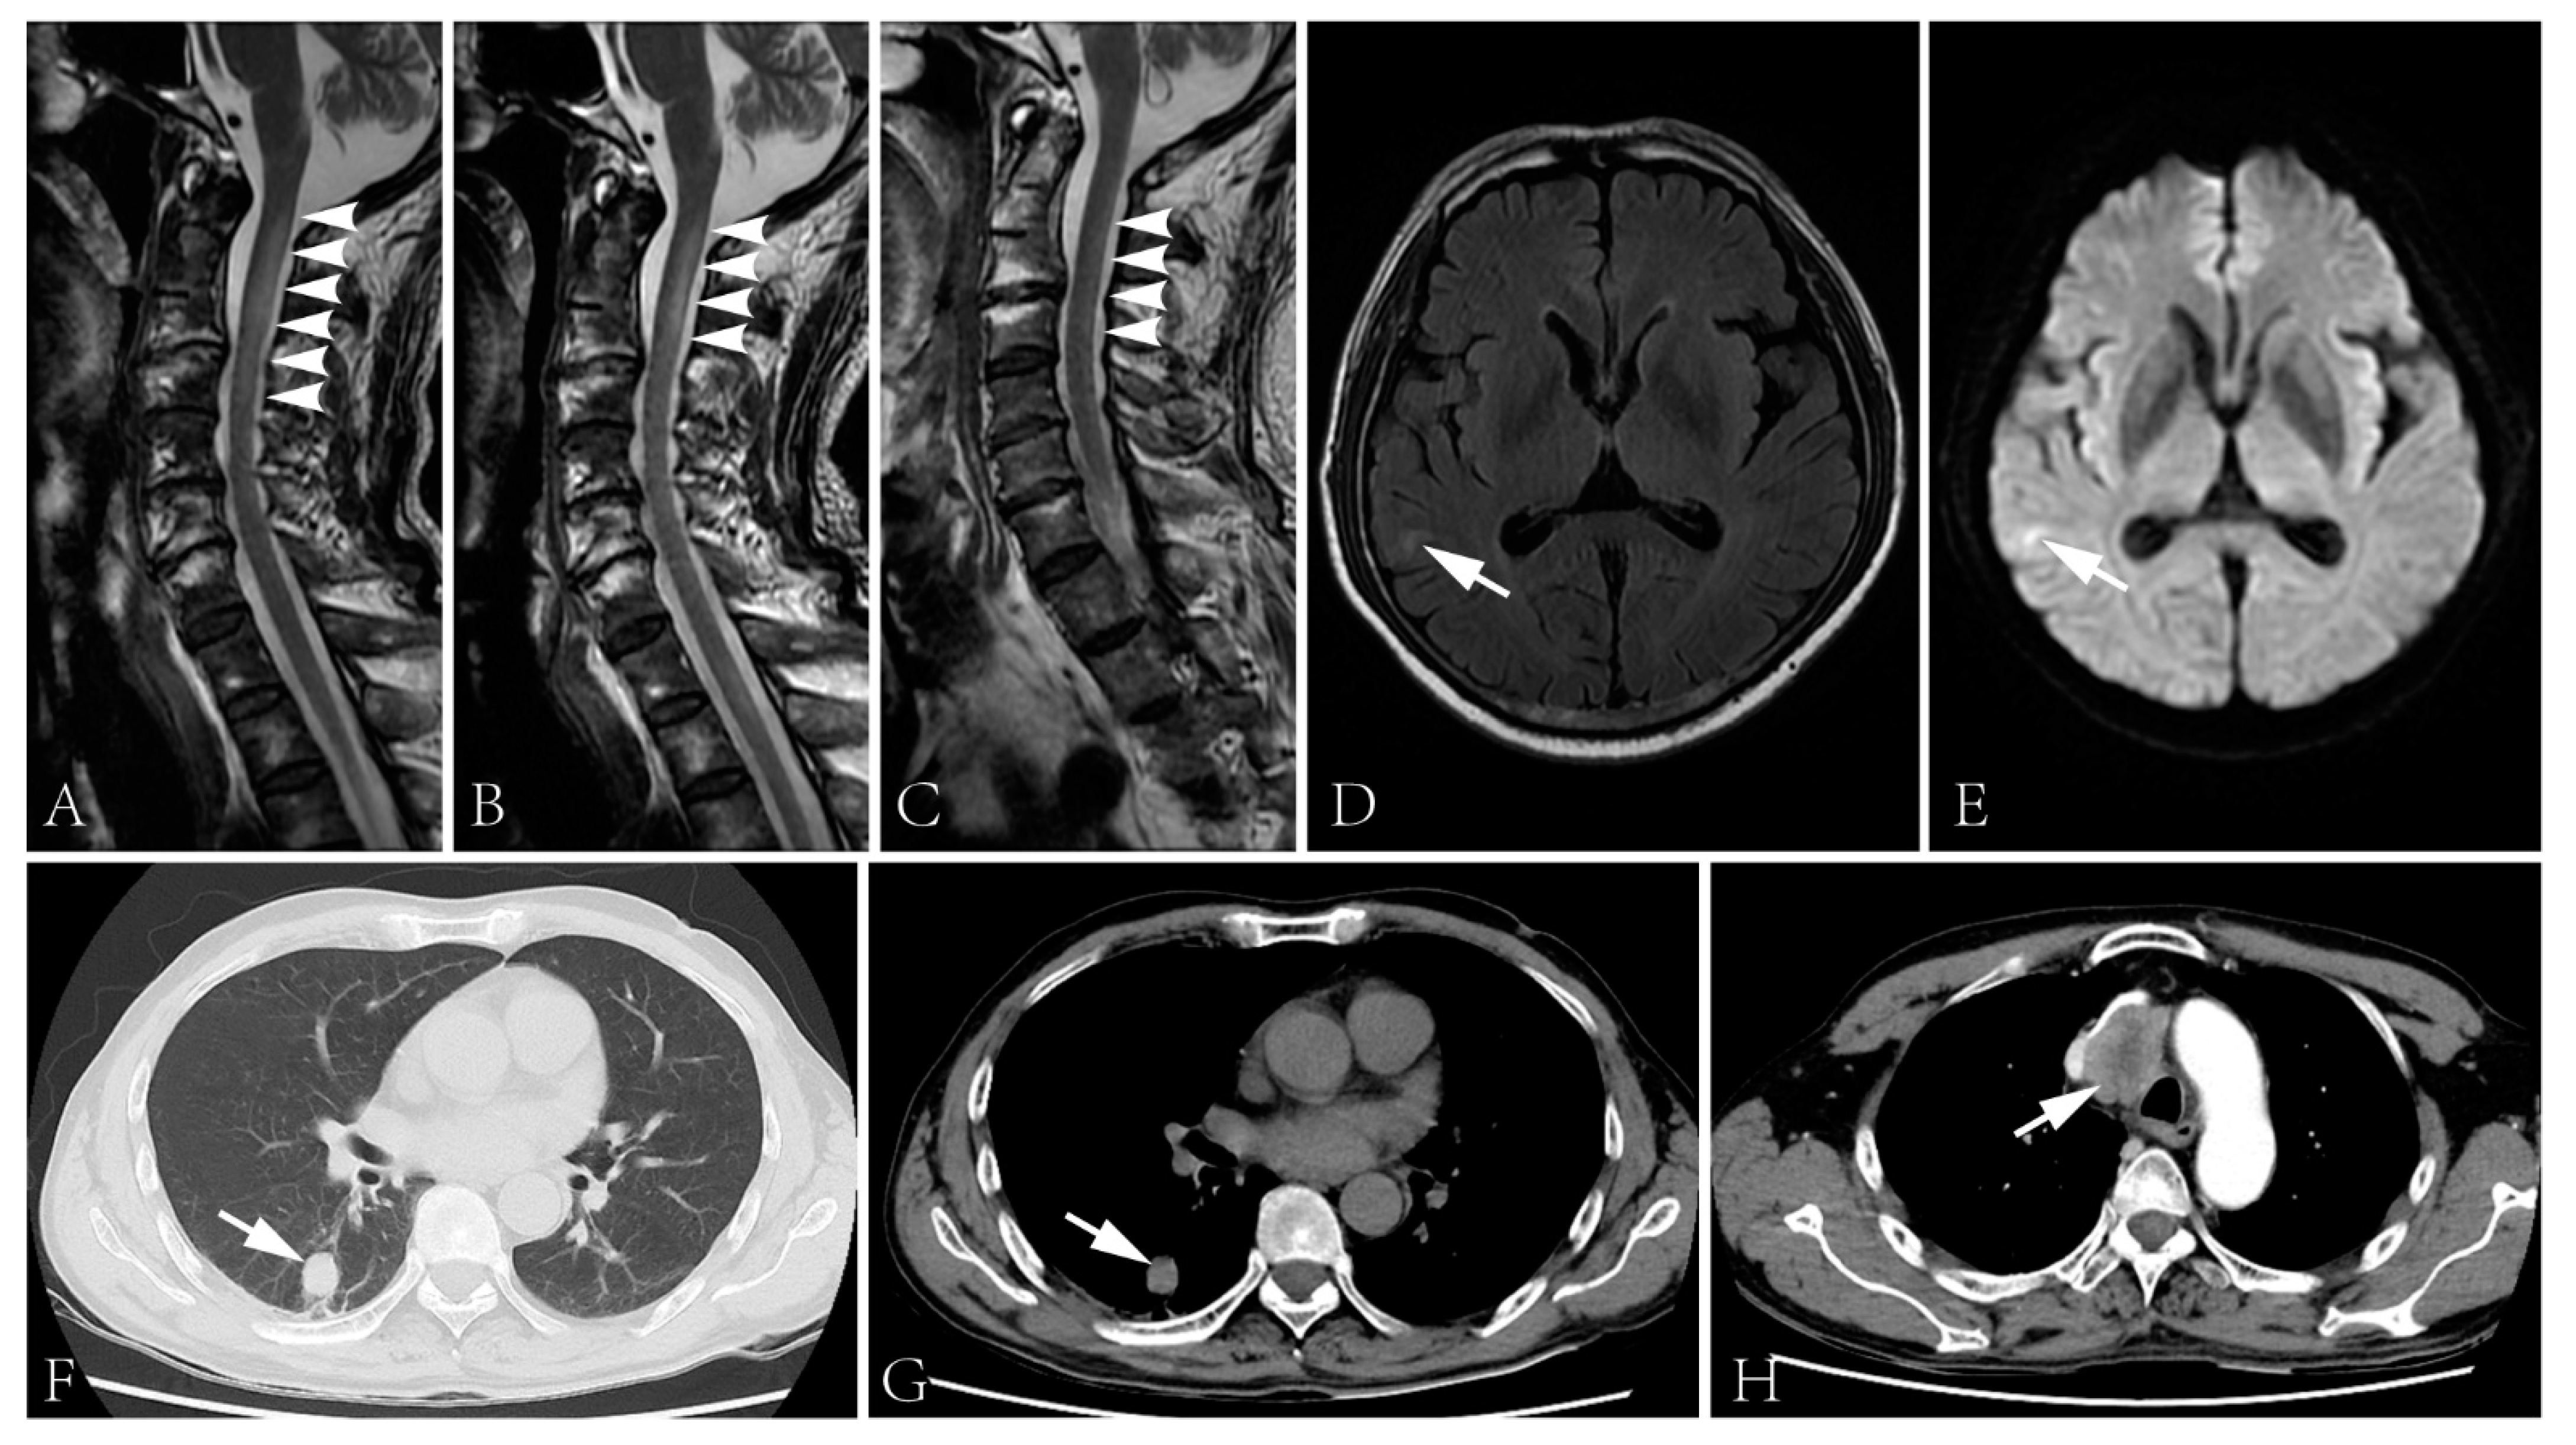

Figure 1.

(A–C) Binding of patient’s serum to HEK cells transfected with NF186 (green fluorescence: NF186 protein; red fluorescence: human IgG; blue fluorescence: nucleus). (D) Binding of patient’s serum to HEK cells transfected with CV2 (green fluorescence: human IgG).